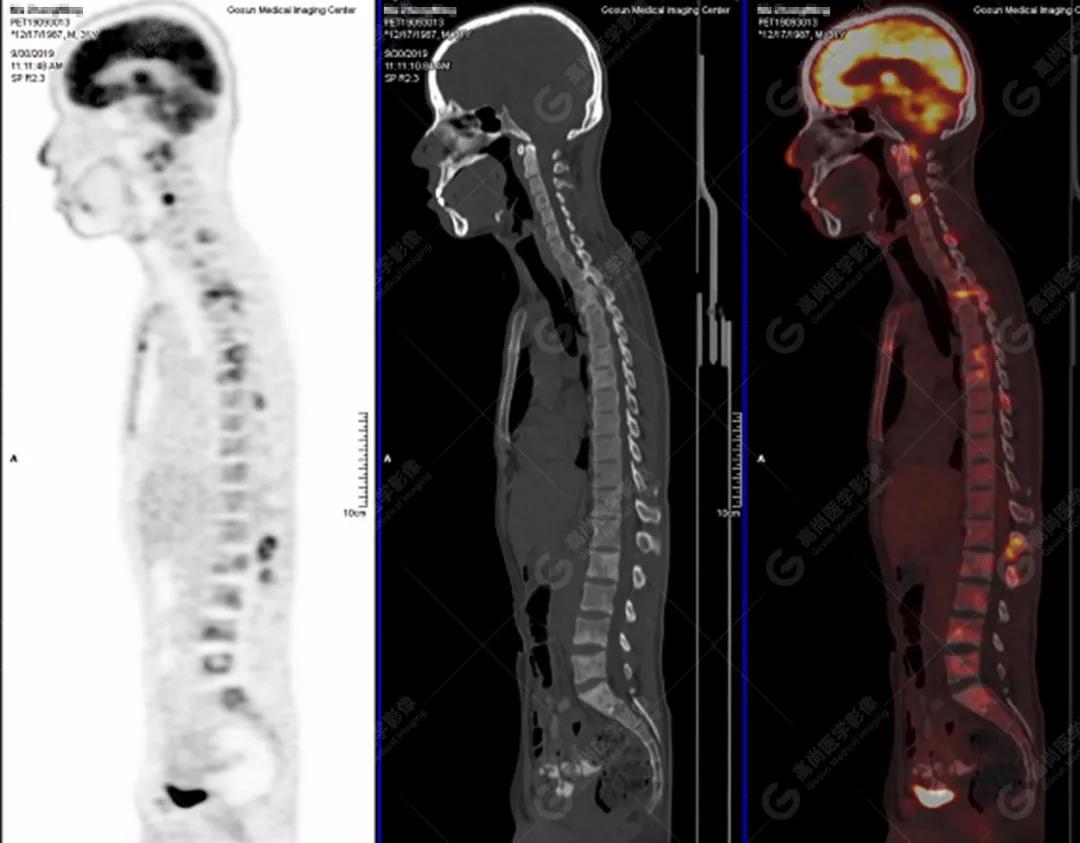

脊柱多發(fā)椎體及附件骨質破壞,代謝不均性增高

全身多處骨質破壞,代謝不均性增高

骨結核:好發(fā)青少年,好發(fā)部位為脊柱,又稱Pott病,表現(xiàn)為椎體松質骨破壞,骨皮質失去完整性,可見死骨和輕微骨增生和塌陷,早期椎間盤無破壞,后期發(fā)生破壞,椎間隙變窄,可伴椎旁冷膿腫,其次是膝、髖、肘關節(jié)。